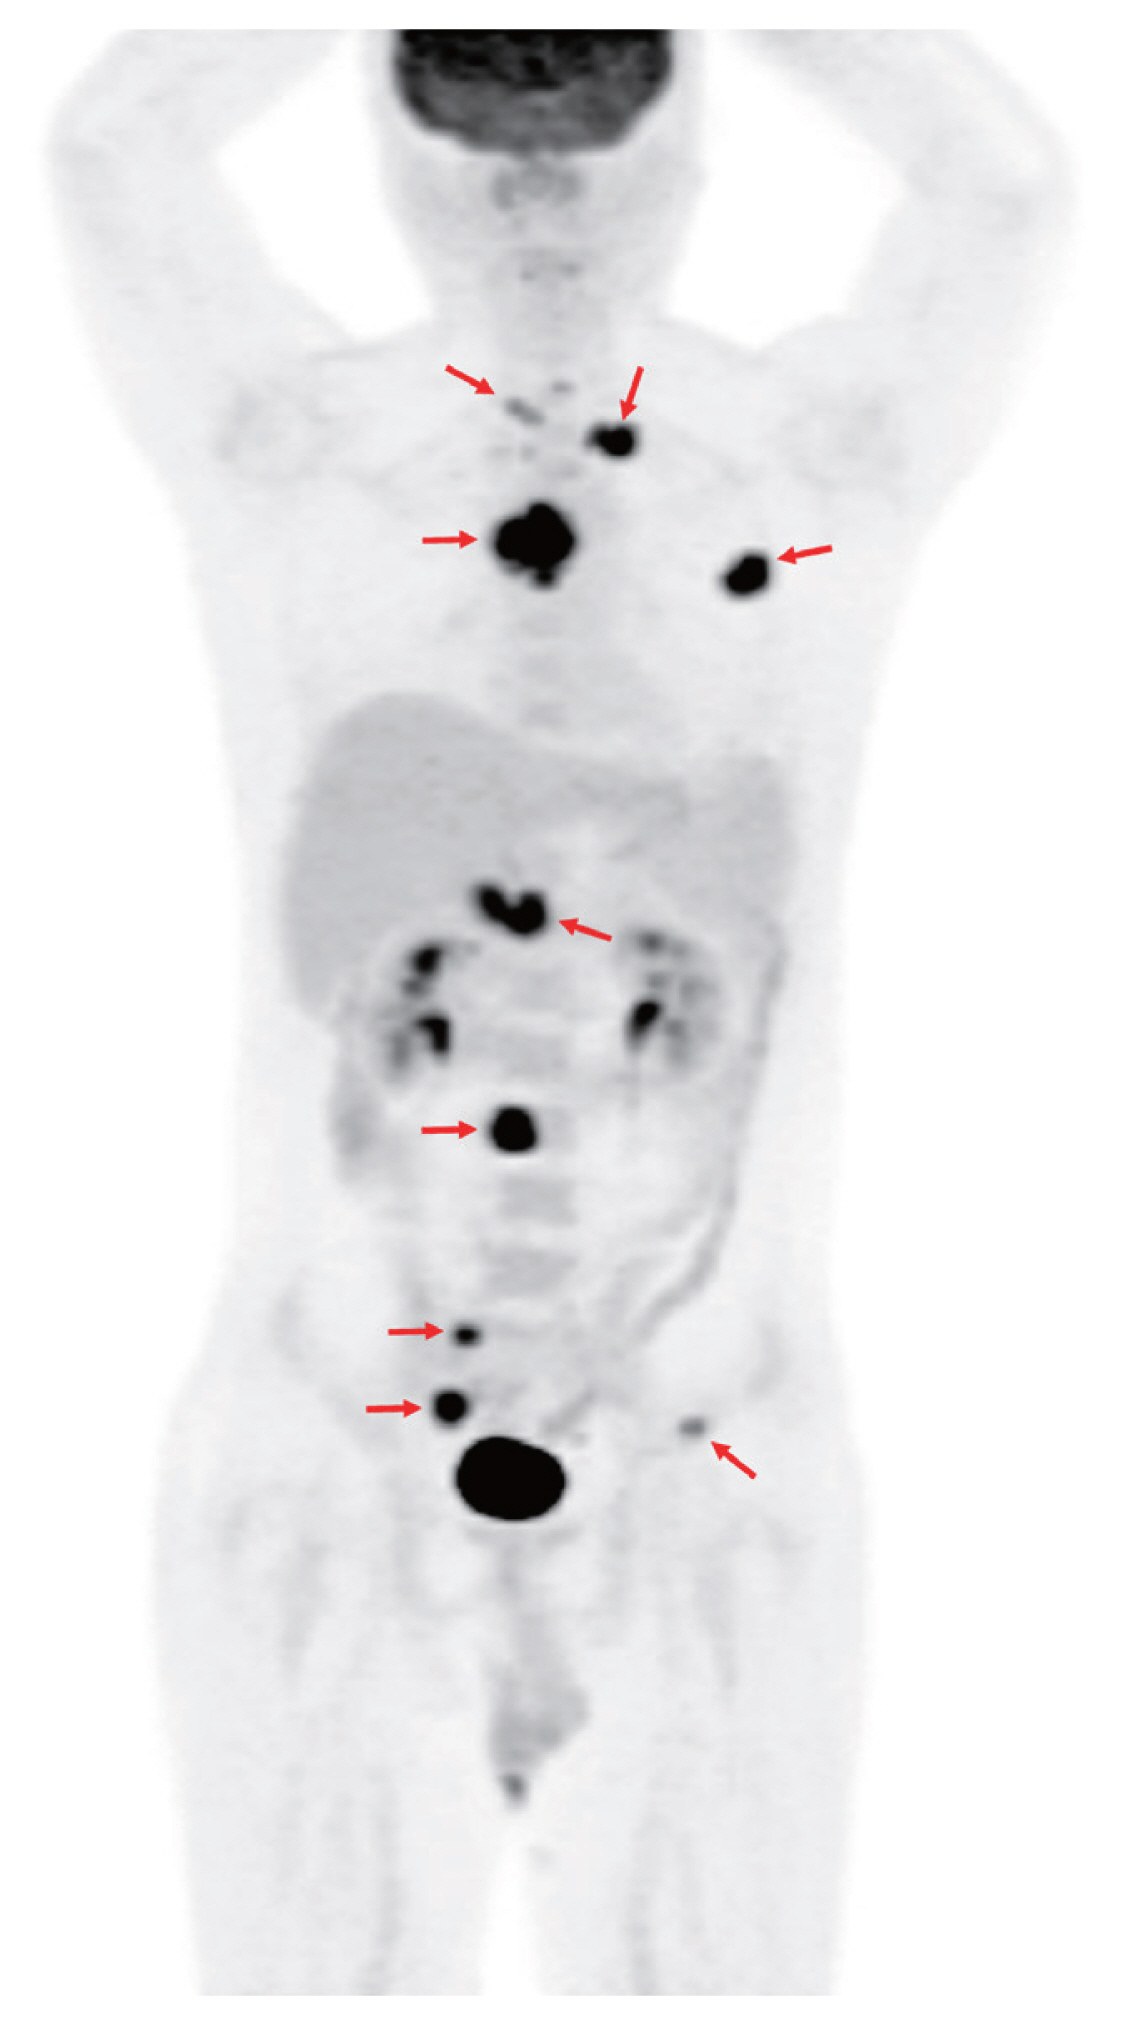

A 32-year-old man without underlying diseases presented to the emergency department with an abrupt onset of gait disturbances and a 4-week history of back pain. The patient was afebrile, and all laboratory findings were normal. Rapid plasma reagin test for syphilis was negative. Whole-spine magnetic resonance imaging revealed an abnormal signal intensity with contrast enhancement at levels T3-T5 and level L3 (Fig. 1), as well as in the right sacral alar portion and left second rib (not shown). However, chest computed tomography (CT) showed no abnormalities in the lung parenchyma, airways, pleura, or lymph nodes. Bone scan suggested bone metastases in the skull, left clavicle, left third rib, and T3-T5 and L3 vertebrae. 18F-fluorodeoxyglucose (18F-FDG) positron emission tomography/CT showed intense FDG uptake in multiple bone lesions and portocaval areas, possibly bone metastases and metastatic lymphadenopathy (Fig. 2). Percutaneous transpedicular bone biopsies were performed in the T4 and L3 vertebral bodies. Histopathological findings revealed chronic granulomatous inflammation with necrosis; however, acid-fast bacilli staining and duplex real-time polymerase chain reaction for Mycobacterium tuberculosis complex and non-tuberculous mycobacteria from fresh bone tissue were negative. On the fifteenth day after the biopsy, the mycobacterial culture from the bone specimens tested positive for M. tuberculosis complex.

Maximal intensity projection image of whole-body 18F-fluorodeoxyglucose (18F-FDG) positron emission tomography/computed tomography shows intense FDG uptake in the T4 vertebral body (maximum standardized uptake value corrected for lean body mass, 14.7) and focal FDG uptake in the left second and third ribs, T1 and L3 vertebral bodies, portocaval and peripancreatic area, right sacral bone, and left iliac bone (red arrows).